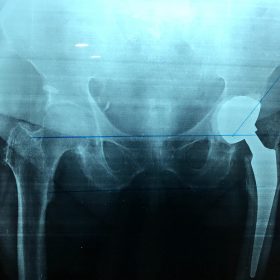

Διάγνωση- Σταδιοποίηση

Διακρίνονται σε 4 στάδια.

Στάδιο Ι. Στένωση του μεσαθριου διαστήματος

Στάδιο ΙΙ. Σκλήρυνση του υποκύμενου χόνδρου

Στάδιο ΙΙΙ. Σκλήρυνση του υπερκείμενου χόνδρου, καταστροφή του υποχόνδρινου οστούν, σχηματισμός οστεόφυτων, οίδημα αρθρώσεως και βραδυνός πόνος

Στάδιο IV. Οστική καθίζηση, καταστροφή μαλακών μορίων μυϊκών ομάδων, υπεξάρθρημα της αρθρώσεως και αλλαγή του μηχανικού άξονα